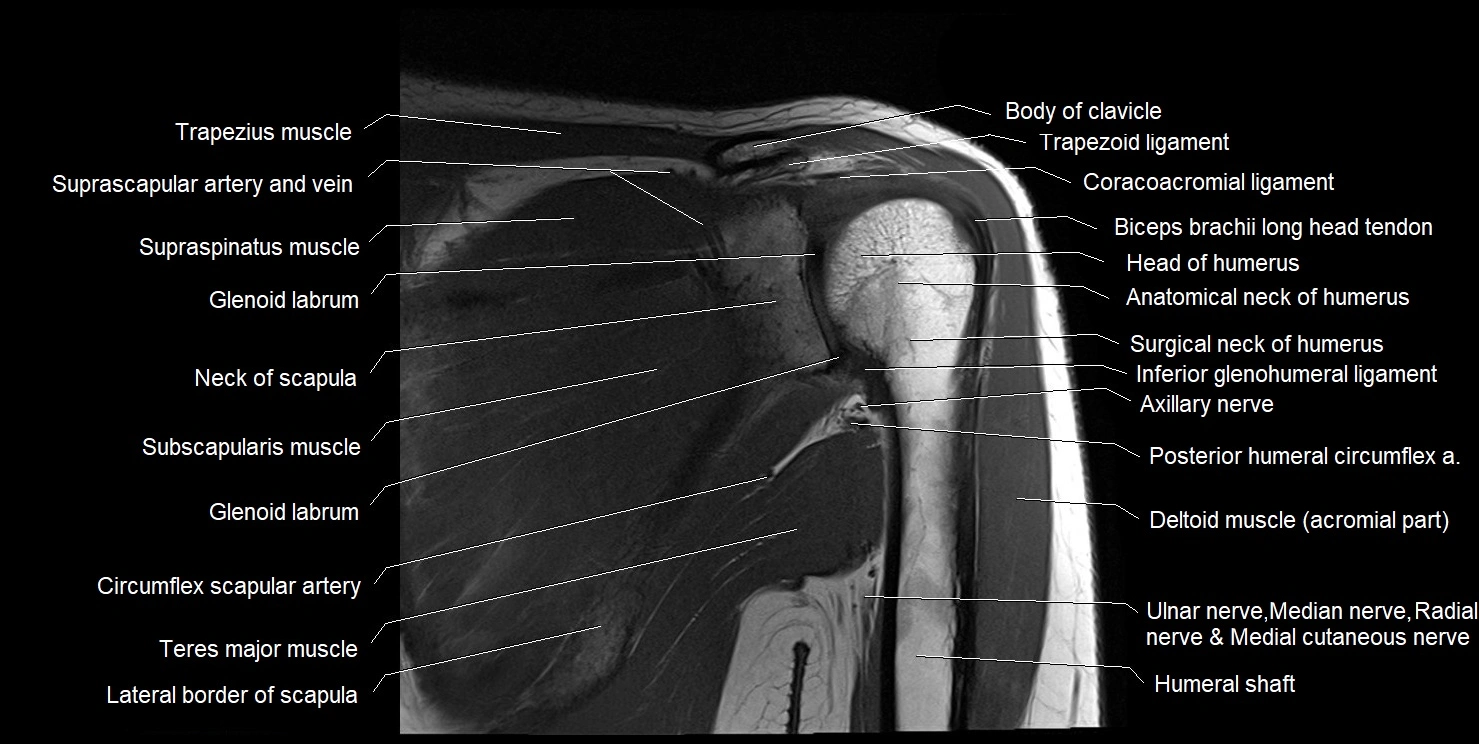

MRI images

image